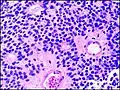

Микроскопический вид типичной нейробластомы с образованием розеток

Гистопатологический образец нейробластомы с розетками Гомера Райта, окраска гематоксилин-эозин